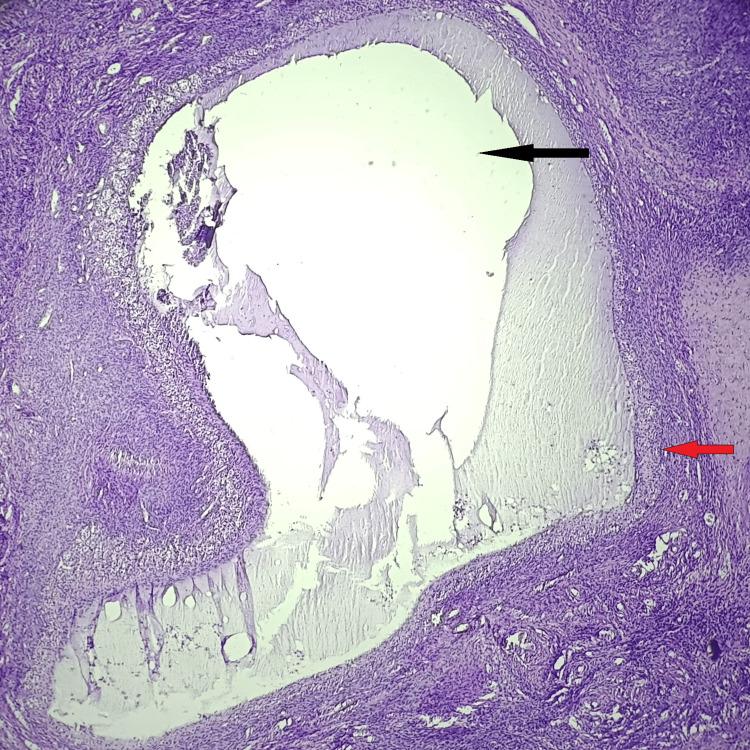

Introduction The uterus is a crucial reproductive organ that is susceptible to the development of several non-neoplastic and neoplastic diseases in women, greatly increasing morbidity and mortality. Although there are various therapeutic options, hysterectomy is still a popular treatment option throughout the world. Abnormal uterine bleeding, pelvic pain, pelvic inflammatory disease (PID), prolapse of the uterus, adenomyosis, endometriosis, fibroids, gynecological malignancies, and obstetric problems that require hysterectomy, all samples must be examined histopathologically. Histopathological examination of the specimens obtained after hysterectomy is important for both diagnosis and treatment. The current work aimed to identify the various clinical indications, analyze the clinicopathological correlation in hysterectomy specimens, and analyze the patterns of lesions in hysterectomy specimens. Materials and methods This study was conducted in the Department of Pathology at the Datta Meghe Medical College, Wanadongari, Nagpur, from February 2022 to January 2023. All types of hysterectomy specimens received during this year were examined, and the tissues were processed and stained with H&E. Histopathological examination was performed, and various lesions in the hysterectomy specimens were examined. The study included all forms of hysterectomy, including abdominal, vaginal, laparoscopic, and total abdominal hysterectomy. Results An analysis of 110 cases of hysterectomy revealed that abdominal hysterectomy was the type of hysterectomy in 79 (71.82%) cases, with a maximum age range of 35 to 45 years (42.72%). The proliferative phase endometrium was the most common endometrial pathology, accounting for 43 (39.09%) cases, followed by the atrophic endometrium in 35 (31.82%) cases. Leiomyoma was the most prevalent myometrial lesion, accounting for 52 (47.28%) cases, followed by adenomyosis, accounting for 23 (20.91%) cases. Chronic cervicitis was the most common incidental finding in the hysterectomy samples, accounting for 85 (77.28%) cases. Follicular cysts, representing 22 (20%) cases, were the most common ovarian lesions, followed by serous cystadenoma in seven (6.37%) cases. Two cases of malignant tumors were noted: one case of endometrial carcinoma and one case of mucinous cystadenocarcinoma of the ovary. In most cases, ranging from 70% to 100%, the final histopathological diagnosis supports the preoperative clinical diagnosis. Conclusion Hysterectomy is the most common major gynecological surgery performed under elective conditions. Although histological studies and clinical diagnoses are closely correlated, several lesions, including chronic cervicitis and adenomyosis, were discovered incidentally. Therefore, every hysterectomy specimen must undergo a thorough histological investigation, even if it appears superficially normal, to confirm the diagnosis and improve postoperative care.

对110例子宫切除术病例的分析显示,79例(71.82%)为腹部子宫切除术,最大年龄范围为35至45岁(42.72%)。增殖期子宫内膜是最常见的子宫内膜病理类型,占43例(39.09%),其次是萎缩性子宫内膜35例(31.82%)。平滑肌瘤是最常见的肌层病变,占52例(47.28%),其次是子宫腺肌病,占23例(20.91%)。慢性宫颈炎是子宫切除标本中最常见的偶然发现,占85例(77.28%)。滤泡囊肿占22例(20%),是最常见的卵巢病变,其次是浆液性囊腺瘤7例(6.37%)。发现2例恶性肿瘤:1例子宫内膜癌和1例卵巢黏液性囊腺癌。在大多数情况下,从70%到100%,最终的组织病理学诊断支持术前临床诊断。